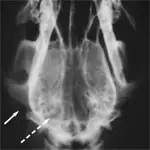

Dorsoventral View

1. Air shadows in the external ear canals (arrow) help with orientation, but distortion that masks the bullae (dashed arrow) occurs because of superimposition of petrous temporal bones.